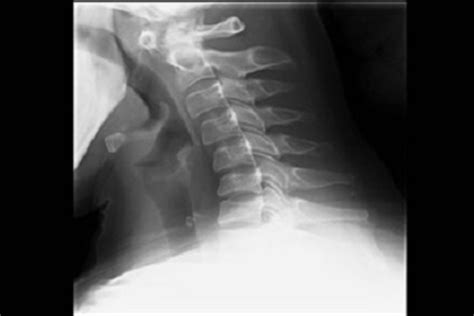

At its core, arthritis in the neck involves the gradual wear and tear of the cartilage, discs, and bones in the cervical spine. Over time, the joints in your neck can deteriorate, leading to inflammation and pain. This condition is very common; in fact, the vast majority of individuals over the age of 60 show some signs of cervical spondylosis on imaging studies, although not everyone experiences noticeable symptoms.

When the cushioning cartilage between the vertebrae breaks down, the bones can begin to rub against each other. This friction often leads the body to produce bone spurs, also known as osteophytes, as a protective mechanism. Unfortunately, these spurs can narrow the space where nerves pass through, potentially leading to pain that radiates into the shoulders, arms, or hands.